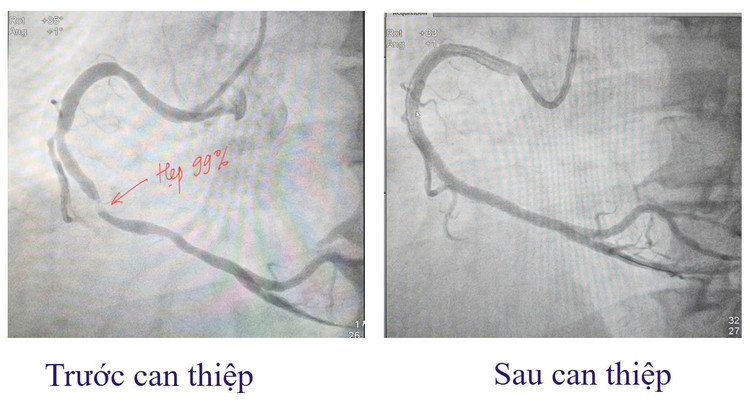

Ngay lập tức, bệnh nhân được cấp cứu theo phác đồ hội chứng vành cấp và chỉ định chụp động mạch vành qua da cấp cứu. Kết quả cho thấy: Động mạch vành phải (RCA) đoạn 2-3 hẹp tới 99%. RCA đoạn 1 hẹp 60%. Đây là tình trạng tắc hẹp mạch vành nguy kịch, có thể dẫn đến hoại tử cơ tim lan rộng và đe dọa tính mạng nếu không được can thiệp tái thông mạch máu kịp thời.

Kíp can thiệp do ThS.BS Đinh Danh Trình, Trưởng khoa Tim mạch, cùng ê kíp đã nhanh chóng tiến hành can thiệp đặt stent mạch vành, tái thông đoạn mạch bị hẹp. Ca can thiệp diễn ra thành công, giúp khôi phục dòng máu nuôi cơ tim, ngăn chặn nguy cơ nhồi máu lan rộng và biến chứng nguy hiểm.